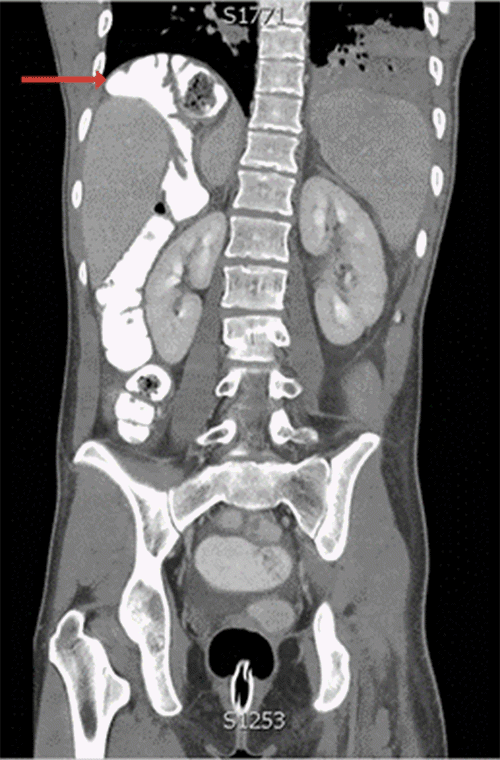

One week after last discharge, the patient returned for the fourth time with recurrent symptoms. Admission CT scan demonstrated Chilaiditi 's sign as well as a twisted proximal colon posterior to the liver (Figure 4). After recommending colectomy to prevent recurrence, the patient agreed to proceed to the operating room.

Figure 4. CT Scan on Fourth Presentation. Published with Permission

A (sagittal), Hepatic flexure interposed posteriorly and medially to the right liver lobe; and B (coronal), hepatic flexure interposed posterior and medial to the right liver lobe, consistent with Chilaiditi syndrome